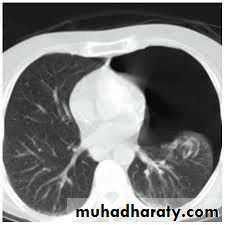

CT scan

BronchoscopyPneumothorax

Emphysema